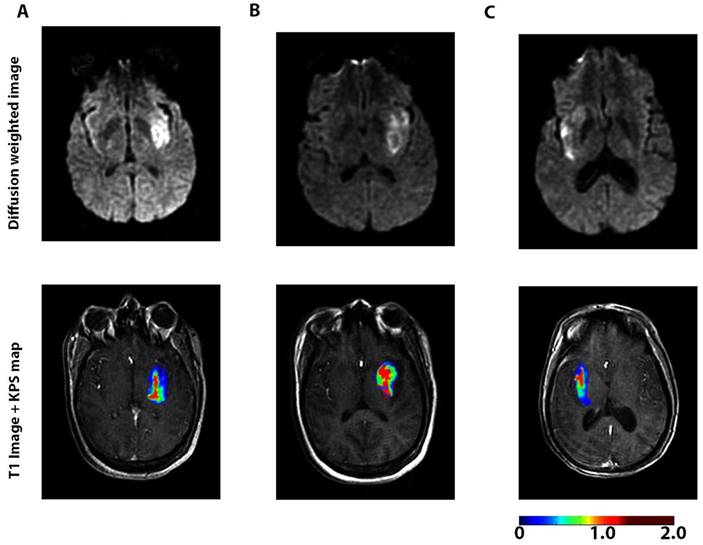

Another major focus is to understand the dynamic change in BBB permeability and its mechanisms in ischemic stroke. When BBB disruption occurs after stroke is controversial. Some studies have suggested that stroke disrupts the BBB several hours after stroke onset [34]. However, a recent study based on enhanced MRI showed that BBB leakage continually increased in patients right after acute ischemic stroke (AIS) (Figure 2) [74].

FIGURE 2

A dynamic contrast-enhanced magnetic resonance imaging (DCE-MRI) sequence was performed with diffusion-weighted imaging to assess blood-brain barrier (BBB) permeability after acute ischemic stroke in 49 patients. The figures represent diffusion-weighted scans (top) and blood-brain barrier permeability maps (bottom) for 3 patients <6 h (A), 6-48 h (B), and >48 h (C) after the onset of stroke symptoms. Elevated permeability-surface area product (KPS; scale: mL/100 g/min) was observed at all time-points, suggesting a sustained increase in BBB permeability after acute ischemic stroke. The BBB permeability was higher within the core of the infarct compared to the periphery of the infarct. A continuous BBB leakage was confirmed with DCE-MRI in humans for up to 90.1 h after acute ischemic stroke. Adapted with permission from reference [74] under the Creative Commons Attribution License. Abbreviations: BBB: blood-brain barrier; DCE-MRI: dynamic contrast-enhanced magnetic resonance imaging.

BBB permeability was highest at 6-48 h after the onset of AIS. BBB degeneration after AIS may lead to pathologic processes such as edema and hemorrhagic transformation [75]. In addition to using imaging technologies, a serial sampling method for CSF was applied to a non-human primate middle cerebral artery occlusion model to evaluate the dynamic change in BBB permeability based on the CSF/serum albumin ratio. The results indicated that BBB disruption occurred rapidly after ischemia and the extent of the disruption was highly correlated with the disease progress [76]. By focusing on the disintegrated BBB, Ishili et al. delivered PEGylated liposomes to the ischemic brain region under cerebral ischemia conditions and at an early phase after the start of reperfusion [77]. Further, the same group loaded Fasudil, a neuroprotectant agent, into the liposomes and combined it with tissue plasminogen activator (tPA) to treat ischemic stroke. The treatment with liposomal Fasudil before tPA showed significant neuroprotective effects [78].